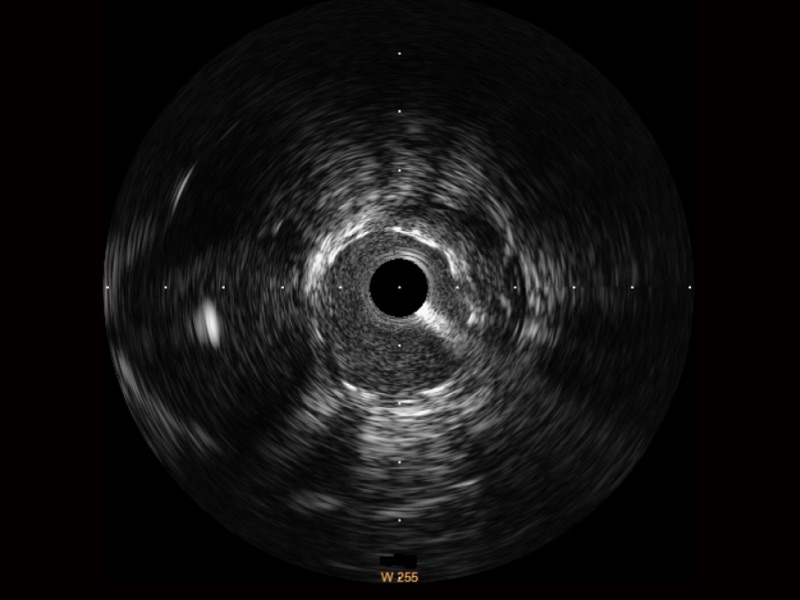

百老汇电子游戏官网宽频IVUS图像

传统IVUS图像

对比传统IVUS导管成像,百老汇电子游戏官网宽频IVUS图像的近场支架梁显影更细腻,远场中膜外血管仍清晰可辨,兼顾远中近,兼顾分辨力与穿透深度